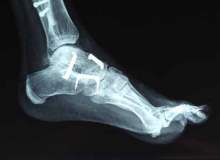

Septik artrit bir eklemdeki son derece ağrılı enfeksiyondur. Bakteriler, veya daha nadir olmak üzere mantarlar, vücudunuzun enfeksiyon kapmış diğer bölümlerinden bir ekleme sıçrayabilir. Bazen bakteriler sadece eklemi etkiler ve vücudun diğer kısımla